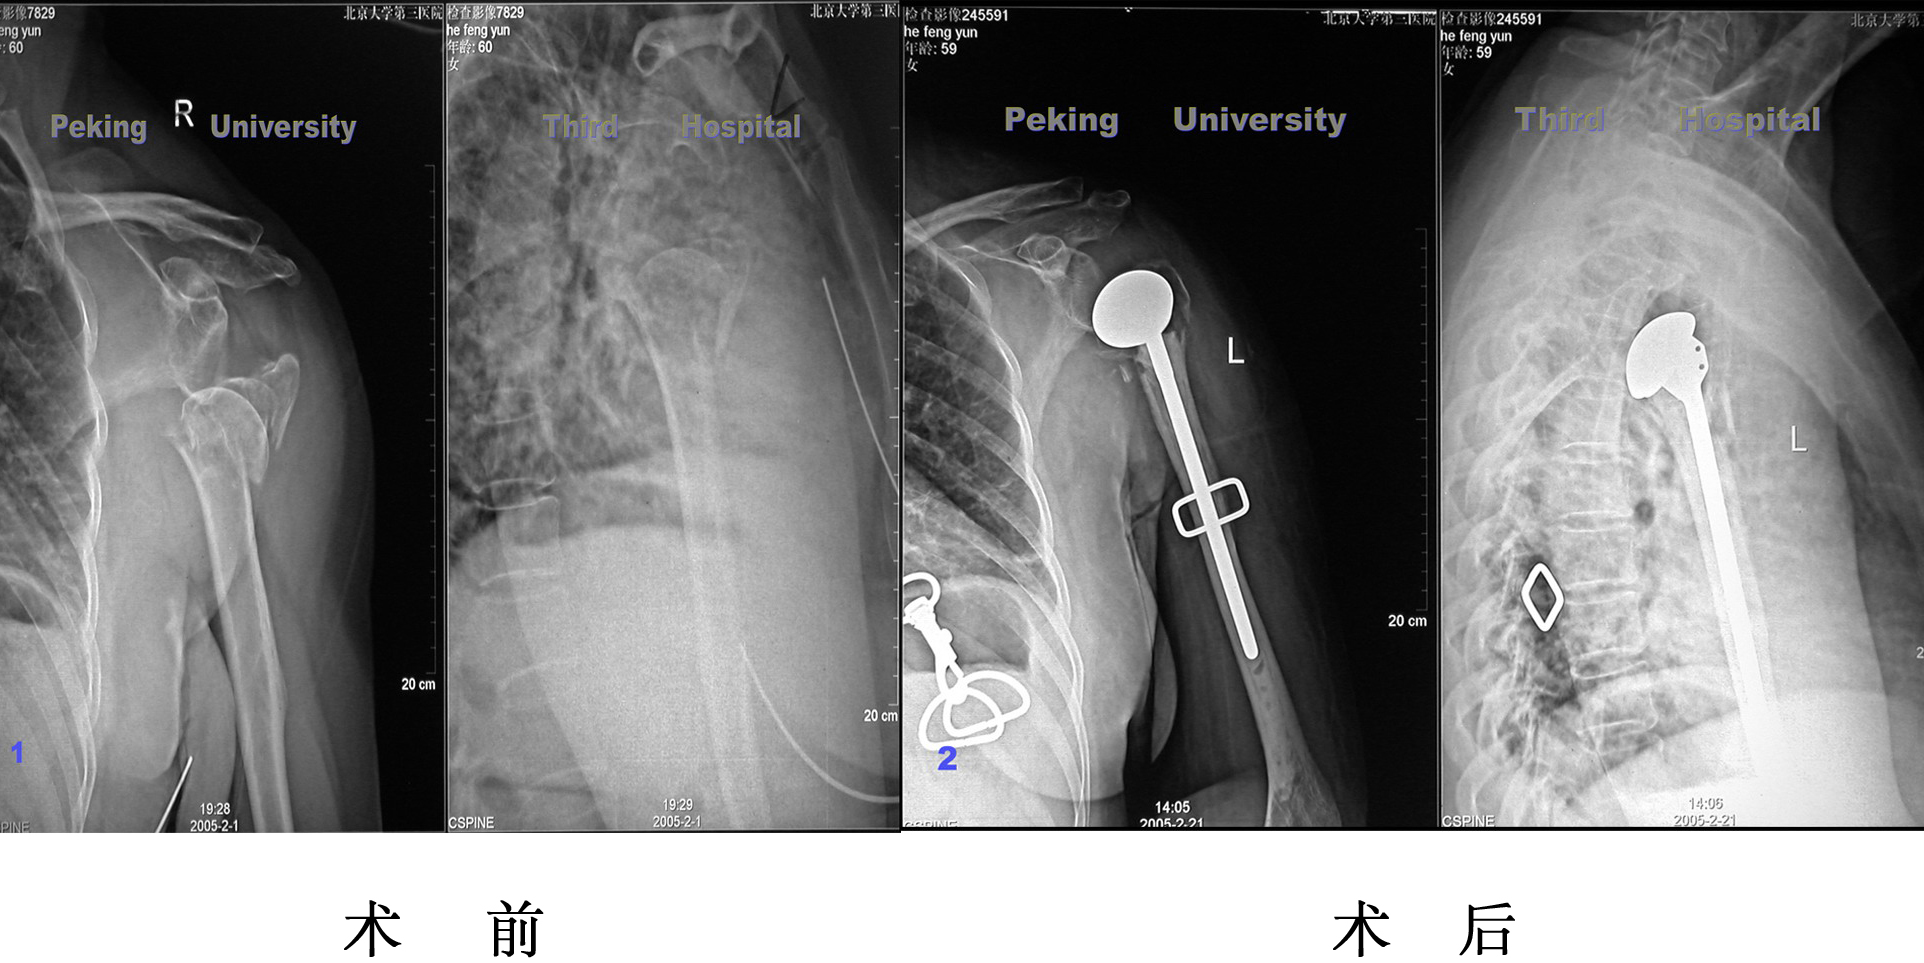

肩关节

肩关节骨折,肩关节置换手术